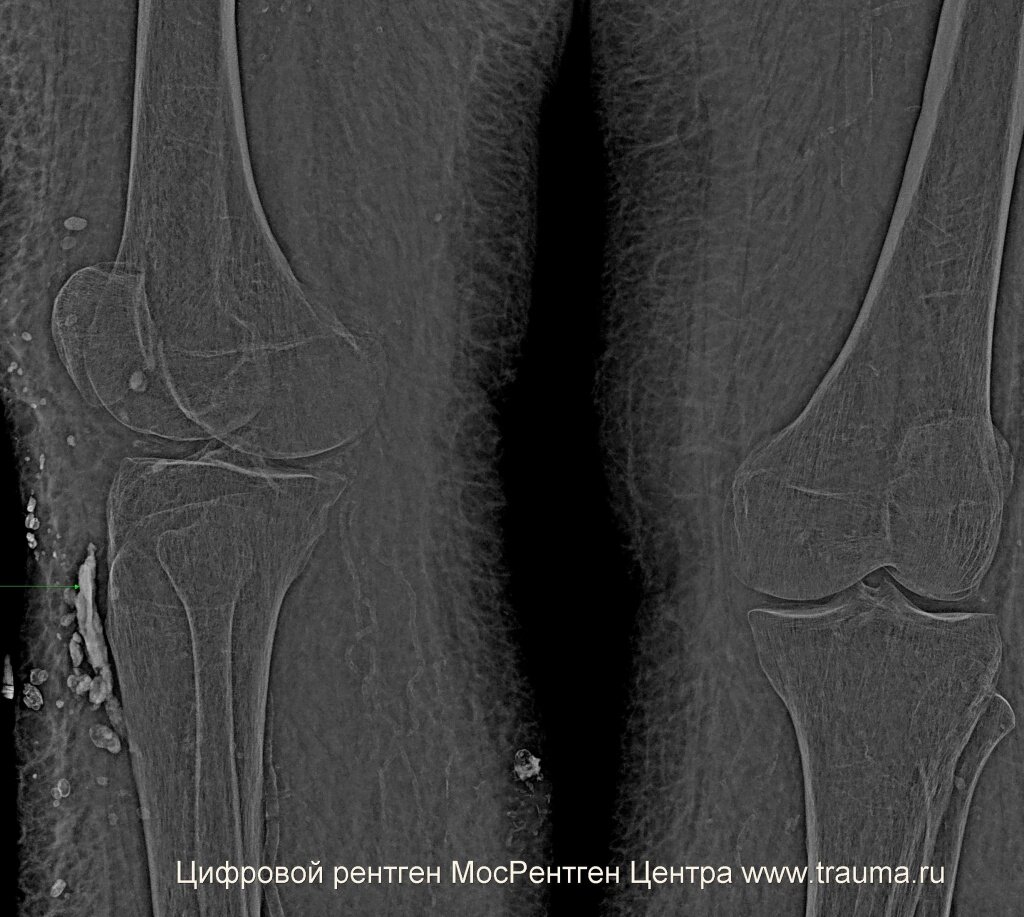

При сохранении сильной боли нужно проконсультироваться у травматолога и сделать рентгенограммы в двух проекциях для исключения перелома костей. Рентген позволяет определить, есть или нет перелом с вероятностью до 99%. Если есть подозрение на перелом, а рентген этого не определяет, можно выполнить компьютерную томографию с построением трехмерного объекта. При повреждении мягких тканей более эффективна магнитно-резонансная томография (МРТ). Какую методику более эффективно применить в каждом случае? Это решает врач.